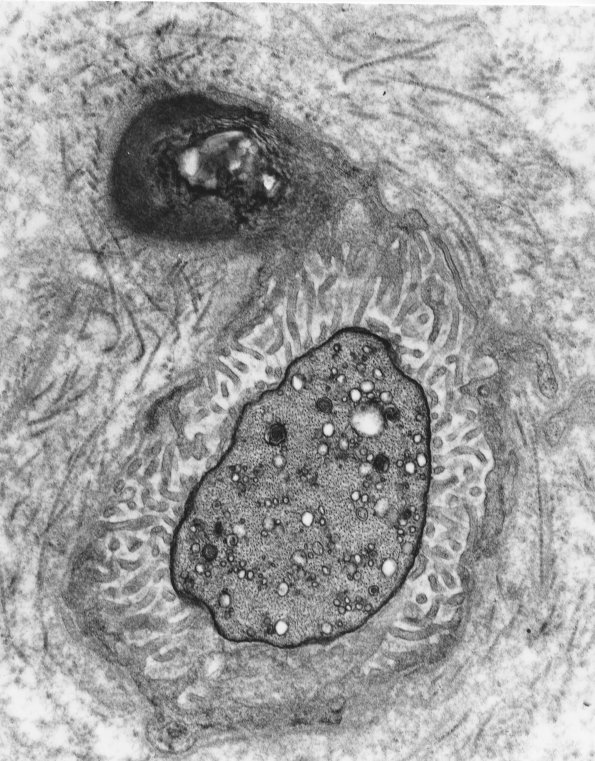

3A1,2 This ultrastructural image taken in cross section through the center of the node shows numerous delicate circumferential Schwannian microvilli. The axon is characterized by a typical appearance with increased density of axoplasm, neurofilaments, microtubules, mitochondria, autophagosomes and endoplasmic reticulum. In many cases the axolemma and circumferential sub-axolemmal density is particularly osmiophilic and thickened. (electron micrographs)